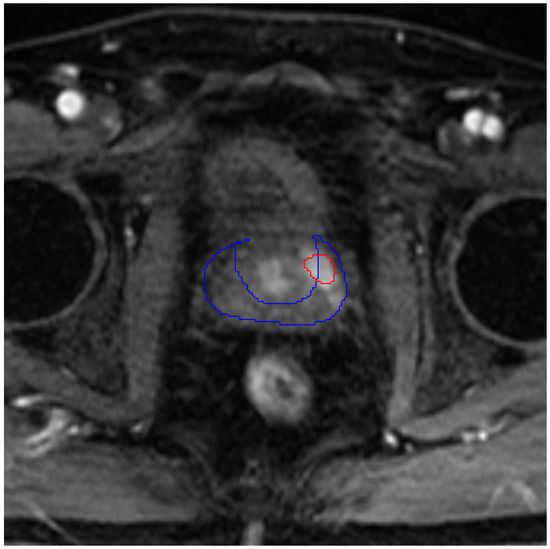

Deep learning models based on supervised learning rely heavily on large annotated datasets and particularly in the context of medical image segmentation, the requirement for pixel-level annotations makes the labeling process labor-intensive, time-consuming and expensive. To overcome these limitations, self-supervised learning (SSL) has emerged as a promising alternative that learns generalizable representations from unlabeled data; however, existing SSL frameworks often employ highly parameterized encoders that are computationally expensive and may lack robustness in label-scarce settings. In this work, we propose a scattering-based SSL framework that integrates Wavelet Scattering Networks (WSNs) and Parametric Scattering Networks (PSNs) into a Bootstrap Your Own Latent (BYOL) pretraining pipeline. By replacing the initial stages of the BYOL encoder with fixed or learnable scattering-based front-ends, the proposed method reduces the number of learnable parameters while embedding translation-invariant and small deformation-stable representations into the SSL pipeline. The pretrained encoders are transferred to a U-Net and fine-tuned for cardiac image segmentation on two datasets with different imaging modalities, namely, cardiac cine MRI (ACDC) and cardiac CT (CHD), under varying amounts of labeled data. Experimental results show that scattering-based SSL pretraining consistently improves segmentation performance over random initialization and ImageNet pretraining in low-label regimes, with particularly pronounced gains when only a few labeled patients are available. Notably, the PSN variant achieves improvements of 4.66% and 2.11% in average Dice score over standard BYOL with only 5 and 10 labeled patients, respectively, on the ACDC dataset. These results demonstrate that integrating mathematically grounded scattering representations into SSL pipelines provides a robust and data-efficient initialization strategy for cardiac image segmentation, particularly under limited annotation and domain shift.